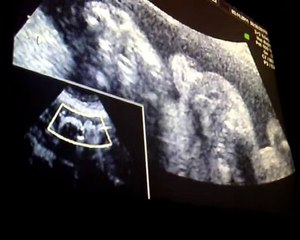

El riguroso entrenamiento de Sol Pérez con 30 semanas de embarazo